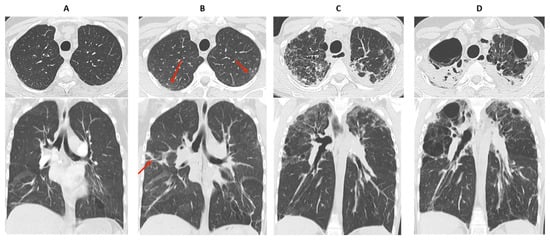

- Hota, P.; Dass, C.; Kumaran, M.; Simpson, S. High-resolution CT findings of obstructive phenotypes of chronic lung allograft dysfunction: More than just bronchiolitis oblierans syndrome. AJR Am. J. Roentgenol. 2018, 211, W13–W21. [Google Scholar] [CrossRef] [PubMed]

- Bankier, A.A.; Van Muylem, A.; Knoop, C.; Estenne, M.; Gevenois, P.A. Bronchiolitis Obliterans Syndrome in Heart-Lung Transplant Recipients: Diagnosis with Expiratory CT. Radiology 2001, 218, 533–539. [Google Scholar] [CrossRef]

- Siegel, M.J.; Bhalla, S.; Guttierrez, F.R.; Hildebolt, C.; Sweet, S. Post-lung transplantation bronchiolitis obliterans syndrome: Usefulness of expiratory thin-section CT for diagnosis. Radiology 2001, 220, 455–462. [Google Scholar] [CrossRef] [PubMed]

- de Jong, P.A.; Dodd, J.D.; Coxson, H.O.; Storness-Bliss, C.; Paré, P.D.; Mayo, J.R.; Levy, R.D. Bronchiolitis obliterans following lung transplantation: Early detection using computed tomographic scanning. Thorax 2006, 61, 799–804. [Google Scholar] [CrossRef]

- Konen, E.; Gutierrez, C.; Chaparro, C.; Murray, C.P.; Chung, T.; Crossin, J.; Hutcheon, M.A.; Paul, N.S.; Weisbrod, G.L. Bronchiolitis obliterans syndrome in lung trnsplant recipients: Can thin-section CT findings predict disease before its clinical appearance? Radiology 2004, 231, 467–473. [Google Scholar] [CrossRef] [PubMed]